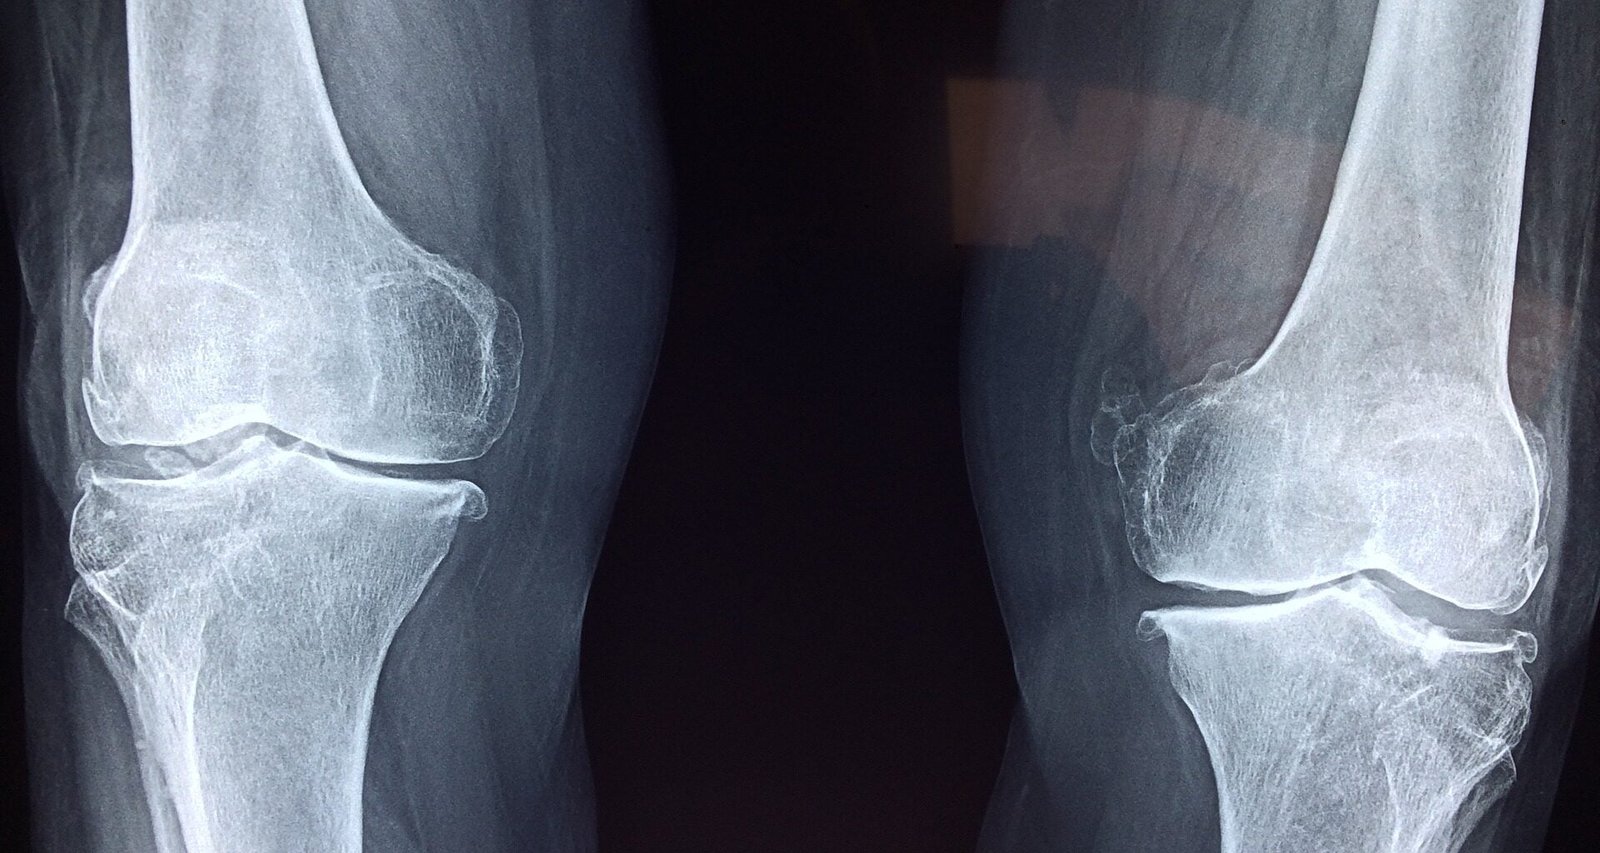

Une des conclusions de l’étude est que, par rapport au groupe non végétarien, les véganes ont un risque relatif de fracture de 1,43, soit une augmentation de 43 %, ce qui aboutit à moins de 2 fractures supplémentaires (dont 1,5 de la hanche) pour un suivi de 1 000 personnes par année. Il n’y a pas de différence significative pour le risque de fractures de la cheville et du poignet entre les personnes véganes et non végétariennes.

Dans cette étude, une augmentation du risque de fracture est surtout observée chez les femmes ménopausées, minces et ne pratiquant que peu ou pas d’activité physique. Cette augmentation du risque est moins forte et non significative chez les hommes, les participant·e·s avec un IMC supérieur à 22,5 et chez les participant·e·s qui avaient un niveau d’activité physique modéré ou élevé.

Les véganes ont la plus faible consommation de calcium alimentaire, mais l’étude montre que seul un quart de l’excès de risque pourrait être attribuable à une déficience en calcium. En effet, le calcium alimentaire n’est pas le seul élément jouant sur la solidité osseuse. D’autres nutriments, incluant les protéines, la vitamine D et possiblement la vitamine B12, contribuent à une bonne santé osseuse. Cette dernière dépend également d’autres facteurs non nutritionnels comme les sollicitations mécaniques : l’os est un organe vivant, en constante reconstruction.